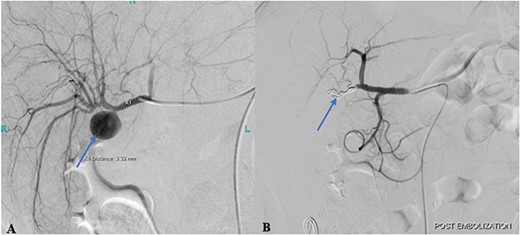

(A) Pre-embolization angiogram of the hepatic artery demonstrates pseudoaneurysm of the cystic artery stump (arrow). (B) Post-coil embolization angiogram of the hepatic artery shows no further filling of the pseudoaneurysm (arrow).

Post-procedural angiogram showed a complete occlusion of the aneurysm and satisfactory filling of the right lobe of the liver through its collaterals from the left hepatic artery (Fig. 2B). Post-procedure hospital stay was unremarkable for any procedure-related complication or hospital-acquired infection. The patient was discharged on the 3rd post-procedure day in stable condition with no output from the abdominal drain.